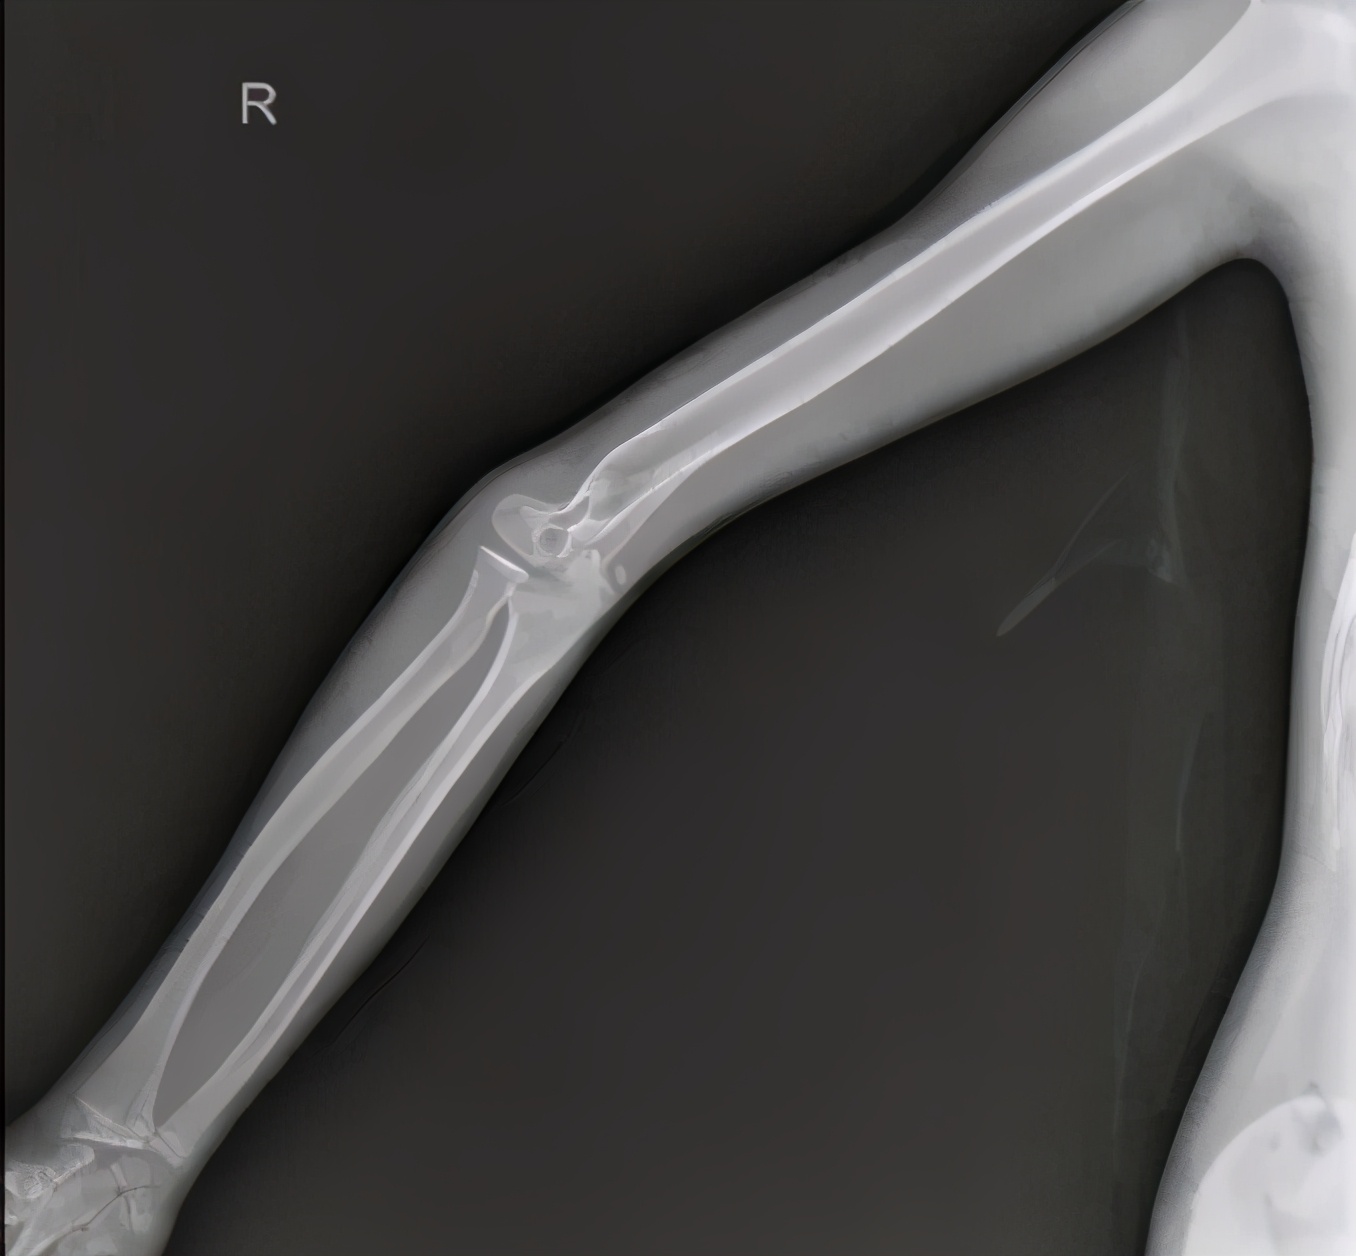

小韩因为8岁时右手肘关节骨折,由于治疗不当,畸形愈合,导致肘内翻畸形。不仅影响美观,而且近几个月来,肘关节部位疼痛,于是前往上海市第六人民医院欧阳元明主任处就诊。

入院检查,肘内翻22度,一定程度的屈肘肌力减弱,并且已经出现了与年龄不相符的关节炎表现,如果不及时手术纠正力线,疼痛症状将会迅速加剧,治疗也将更加棘手。

骨外科欧阳元明主任与团队讨论后,决定行肱骨髁上楔形截骨矫正术,术后上肢力线恢复正常,患者非常满意。